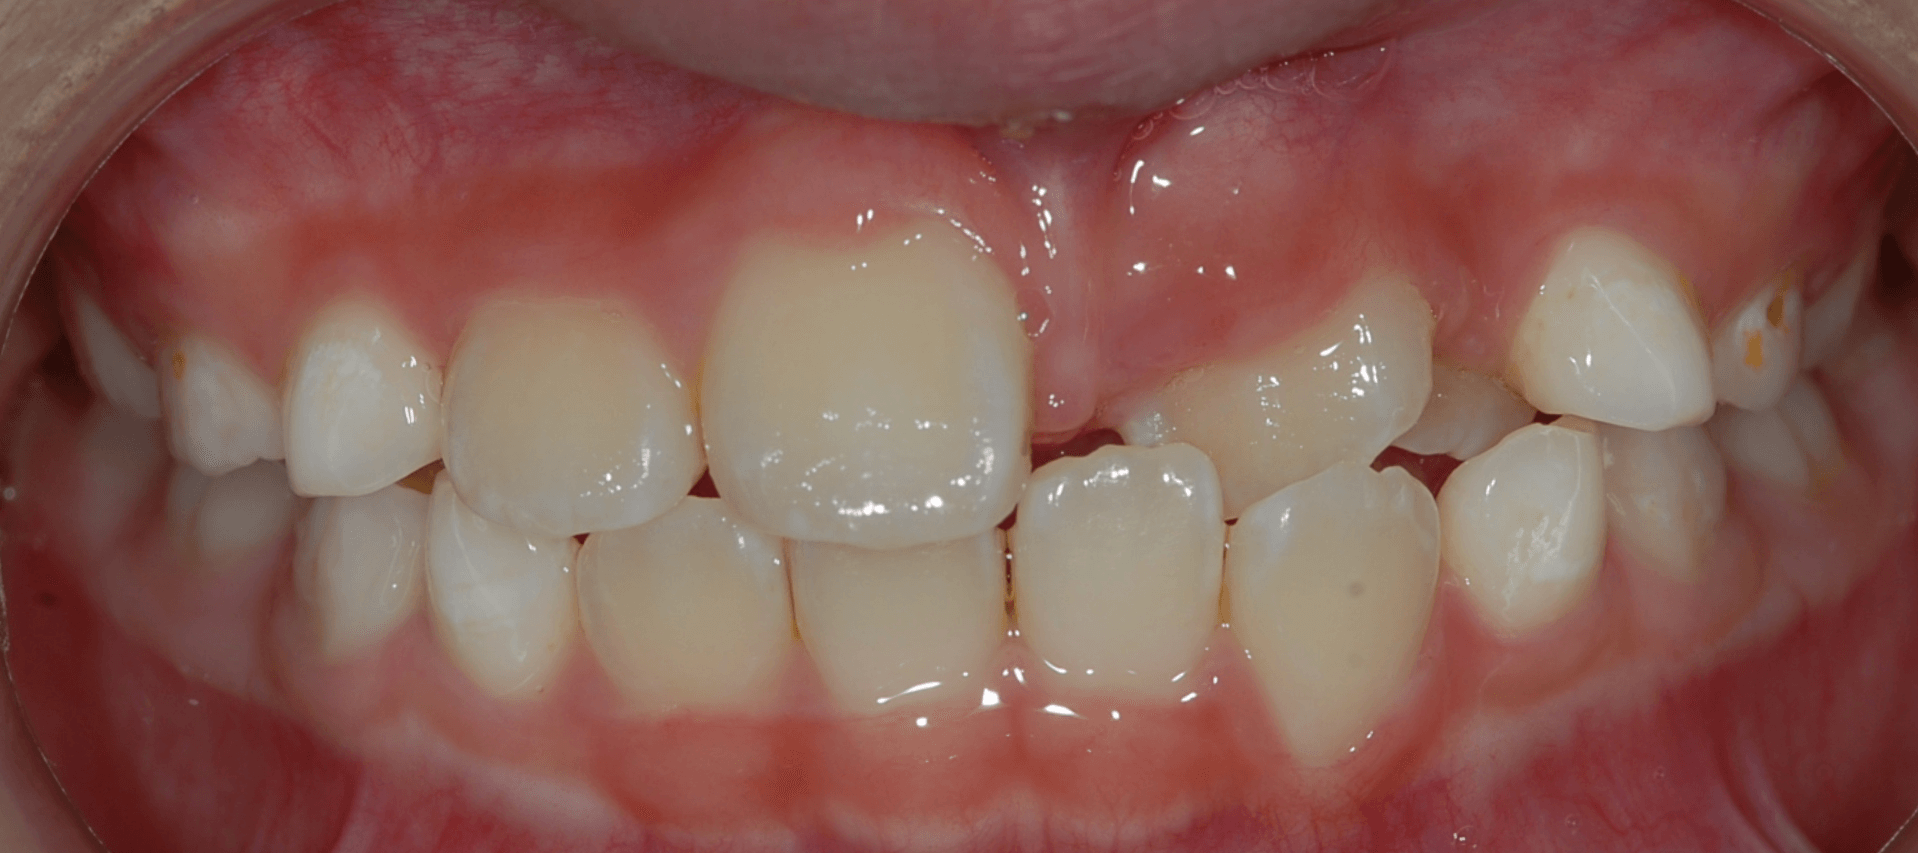

Understanding Early Orthodontic Assessment

Orthodontics is a recognized dental specialty that addresses issues related to the alignment of teeth and jaws. Early assessment may help identify developmental concerns such as spacing, crowding, or bite discrepancies.

The American Association of Orthodontists (AAO) recommends that children receive their first orthodontic evaluation by the age of 7. At this stage, a combination of primary and permanent teeth is present, allowing orthodontists to detect potential concerns early and provide appropriate guidance.

Early evaluations may support timely management of developing issues. Treatment options such as braces, jaw expanders, removable appliances or clear aligners may be considered based on individual clinical needs.

crossbite crooked teeth malocclusion